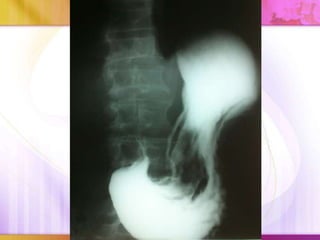

Chụp X quang dạ dày cản quang:

 Dạ dày dãn to

 Hình 3 tầng

 Thuốc không thoát qua

tá tràng

Albumin giảm,Bun,Cre tặng Ion đồ giảm: Cl,Na,Ka,Ca Chụp X quang dạ dày cản quang:  Dạ dày dãn to  Hình 3 tầng  Thuốc không thoát qua tá tràng  Phần hang vị hai bờ vẫn mềm mại(do loét) hay có hình lõi táo (do ung thư hang vị)

Chiếu X-quang: -Hình ảnhtuyết rơi -Sóng nhu động tăng nhanh và mạnh trong giai đoạn tăng trương lực và ngược lại *Lưu ý trước khi chụp phải khám kĩ bệnh nhân để loại trừ thủng tạng và tắc ruột